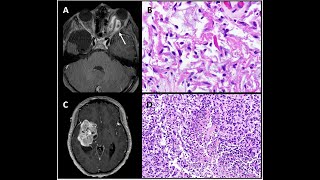

Neurofibroma, Neurofibromatosis-1, and Low Grade MPNST

Learn about the different types of neurofibroma and their pathologic features in this video. I also discuss the scenarios where NF-1 should be considered, the ...